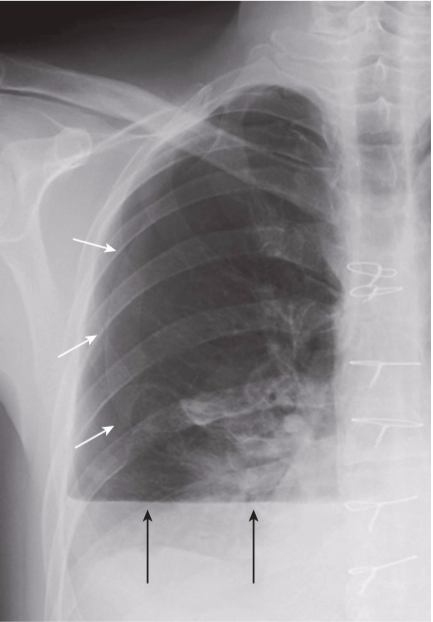

Hydropneumothorax.

hydropneumothorax produces an air-fluid level in the hemithorax marked by a straight edge and a sharp, air-over-fluid interface when the exposure is made with a horizontal x-ray beam (black arrows). This person was stabbed in the right side and there is a moderately large pneumothorax as shown by the visceral pleural white line (white arrows).